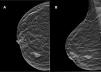

Mujer de 71 años que consultó por un nódulo en el seno derecho. En la exploración física se palpó un nódulo de aproximadamente 2cm en el cuadrante externo de la mama derecha, sin ganglios linfáticos axilares, supraclaviculares o cervicales.

Se realizó una mamografía y ecografía, mostrando una masa irregular de 18mm sin conexión con la piel o el pezón (BIRADS5) (fig. 1A y B).

El CSM es más frecuente en mujeres. Tan solo existen 2 casos masculinos descritos en la literatura13,19, de los cuales solo uno cumple con claridad los criterios para el diagnóstico19. La forma de presentación clínica en la mayoría de los casos es como tumoración palpable en la glándula mamaria. Las pruebas complementarias (mamografía, ecografía y resonancia nuclear magnética) muestran lesiones nodulares, espiculadas, sugestivas de malignidad y nos son de utilidad para descartar afectación de la piel y/o pezón.